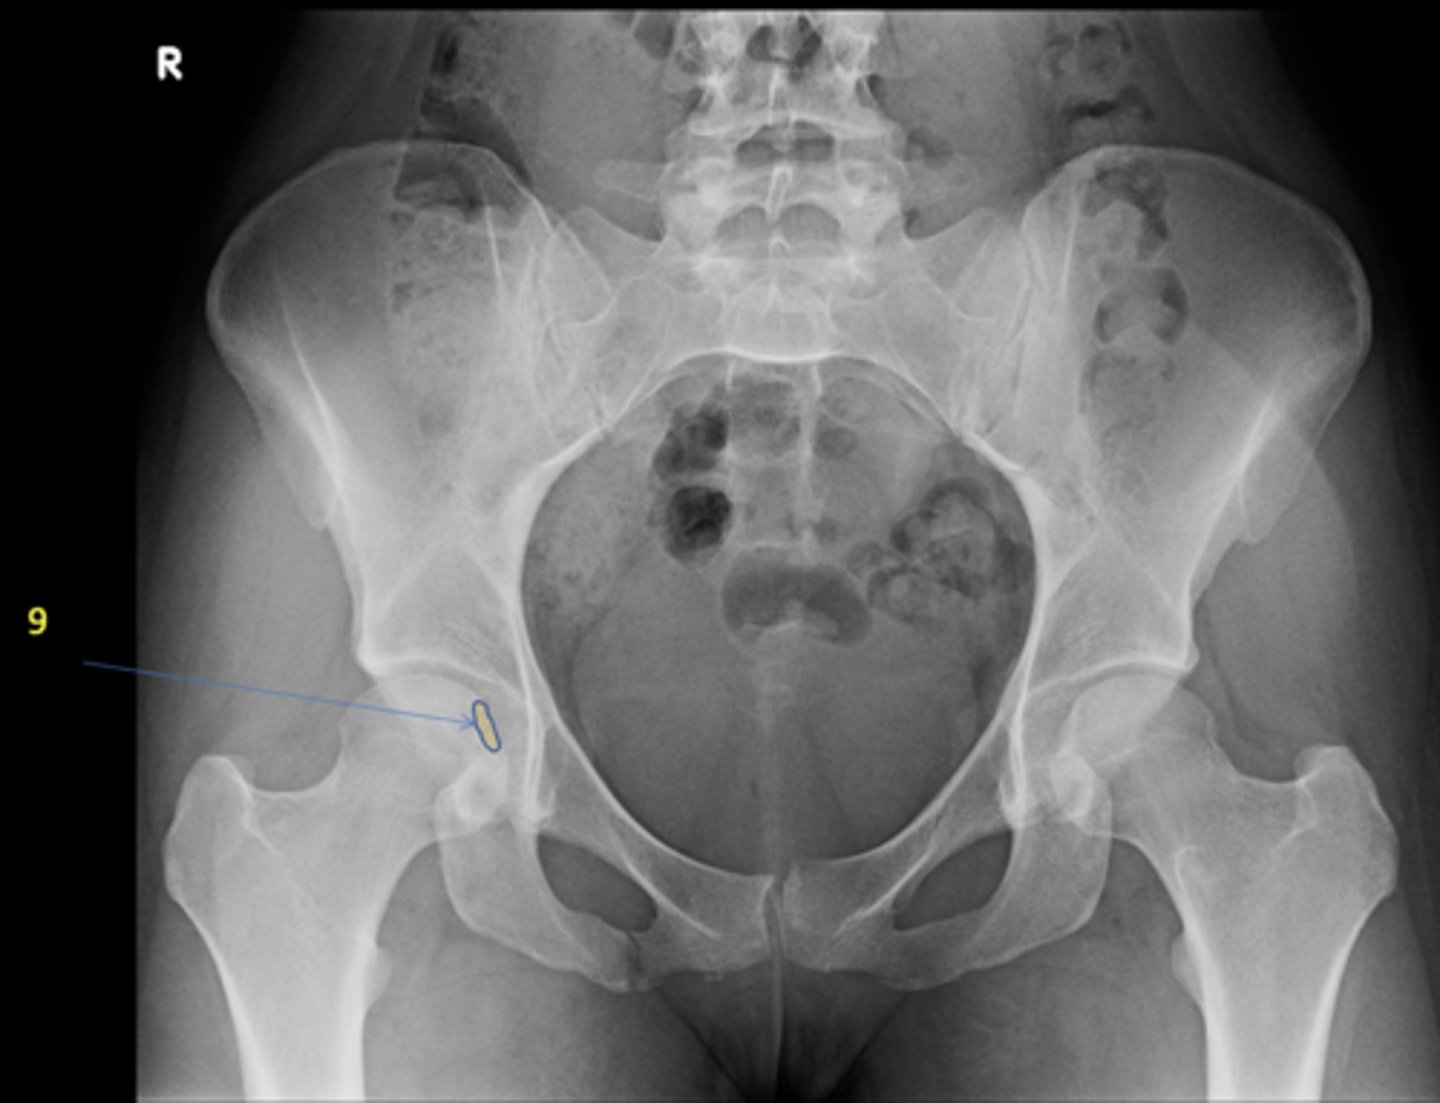

9

New cards

Right fovea capitis

ID 9

<p>ID 9</p>